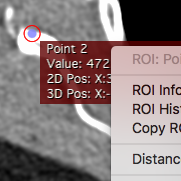

OsiriX 7.5 New features

Click on the thumbnails to have a closer look at each new feature.

Faster GUI

Faster GUI